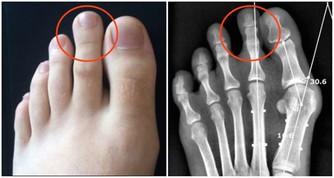

“硫磺椒”能吃嗎?

不能!

某些不良商販為了保存乾辣椒,用硫磺來處理辣椒,即“硫磺椒”。

硫磺椒含有強致癌物,如果進入人體,會給腸胃、食道、粘膜等帶來刺激,

破壞消化系統和呼吸系統。長期食用,還會加大致癌風險。